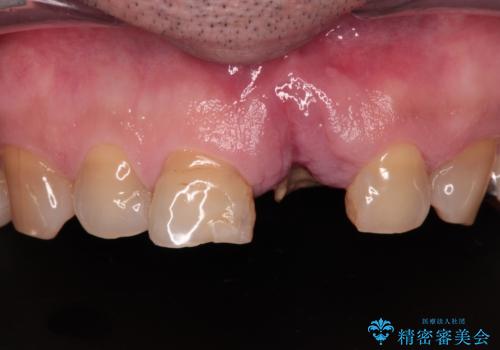

[ 乳歯の残存 ] 前歯のインプラント治療